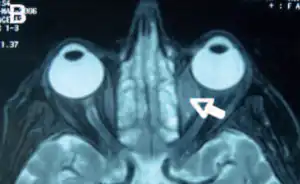

Orbital lymphoma is a common type of non-Hodgkin lymphoma that occurs near or on the eye. Common symptoms include decreased vision and uveitis. Orbital lymphoma can be diagnosed via a biopsy of the eye and is usually treated with radiotherapy or in combination with chemotherapy.